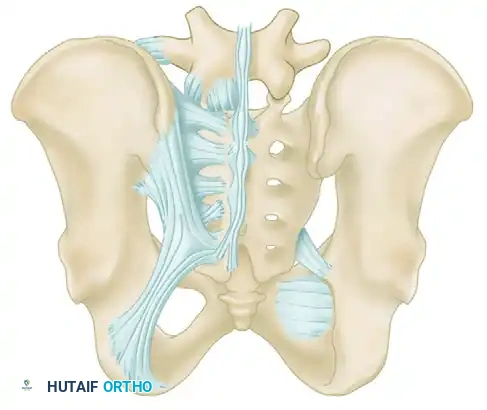

The Posterior Tension Band

The posterior ligamentous complex is the primary weight-bearing and stabilizing structure of the pelvis. Tile famously compared the relationship of the posterior pelvic ligamentous and bony structures to a suspension bridge, with the sacrum suspended securely between the two posterior superior iliac spines.

The critical ligaments include:

* Interosseous Sacroiliac Ligaments: The strongest ligaments in the body, forming the primary restraint to vertical shear forces.

* Anterior and Posterior Sacroiliac Ligaments: Provide rotational stability to the SI joint.

* Sacrotuberous Ligaments: Resist rotation in the sagittal plane (flexion of the sacrum).

* Sacrospinous Ligaments: The primary restraints to external rotation of the hemipelvis.

* Iliolumbar Ligaments: Connect the L5 transverse process to the iliac crest, augmenting vertical and rotational stability.

Biomechanical Restraints

Pelvic stability is determined by these ligamentous structures acting across various planes. The primary restraints to external rotation (the "open book" deformity) are the ligaments of the symphysis, the sacrospinous ligament, and the anterior sacroiliac ligament. Vertical displacement of the hemipelvis is controlled by all the aforementioned structures. However, if the anterior structures are disrupted, vertical stability may still be maintained by intact interosseous sacroiliac, posterior sacroiliac, and iliolumbar ligaments.

Surgical Warning: A rotationally unstable hemipelvis may remain vertically stable due to an intact posterior tension band. Recognizing this distinction is paramount, as it dictates whether the patient requires simple anterior stabilization or complex posterior ring reconstruction.